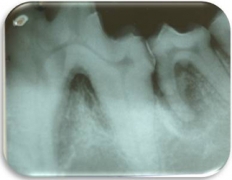

La periodontitis se clasifica como “Periodontitis leve” cuando el tejido óseo se ha destruido máximo en el tercio cervical; “Periodontitis moderada” cuando la destrucción ósea ha llegado al tercio medio de la raíz y “Periodontitis severa” cuando la destrucción ósea ha llegado al tercio apical de la raíz. La movilidad dental ligera aparece en la periodontitis moderada y la movilidad dental excesiva aparece en la periodontitis severa.